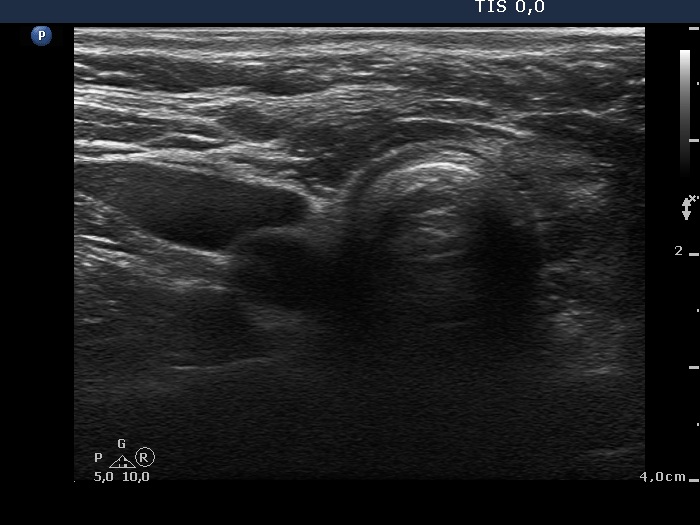

First examination - before surgery (first and second rows of images)

Clinical data: A 58-year-old woman with relapsing hyperthyroidism was managed by another team. She was sent for aspiration cytology. Multiple hypoechogenic nodules were described on ultrasonography.

Ultrasonography. Both lobes were hypoechogenic and contained several hypoechogenic areas do not corresponding to nodules. The echogenicity index was 20%. The vascularization was a bit increased.

Aspiration cytology was performed from one of the hypoechogenic areas in the right thyroid and resulted in benign, hormonal atypia.